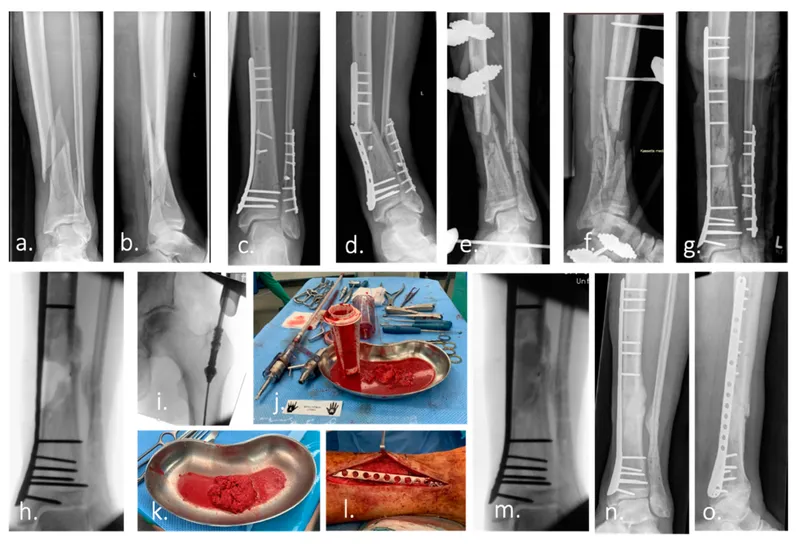

- Fracture Healing: Complex fractures, segmental defects.

⭐ BMPs are crucial for challenging bone healing, especially in recalcitrant nonunions and significant segmental defects.